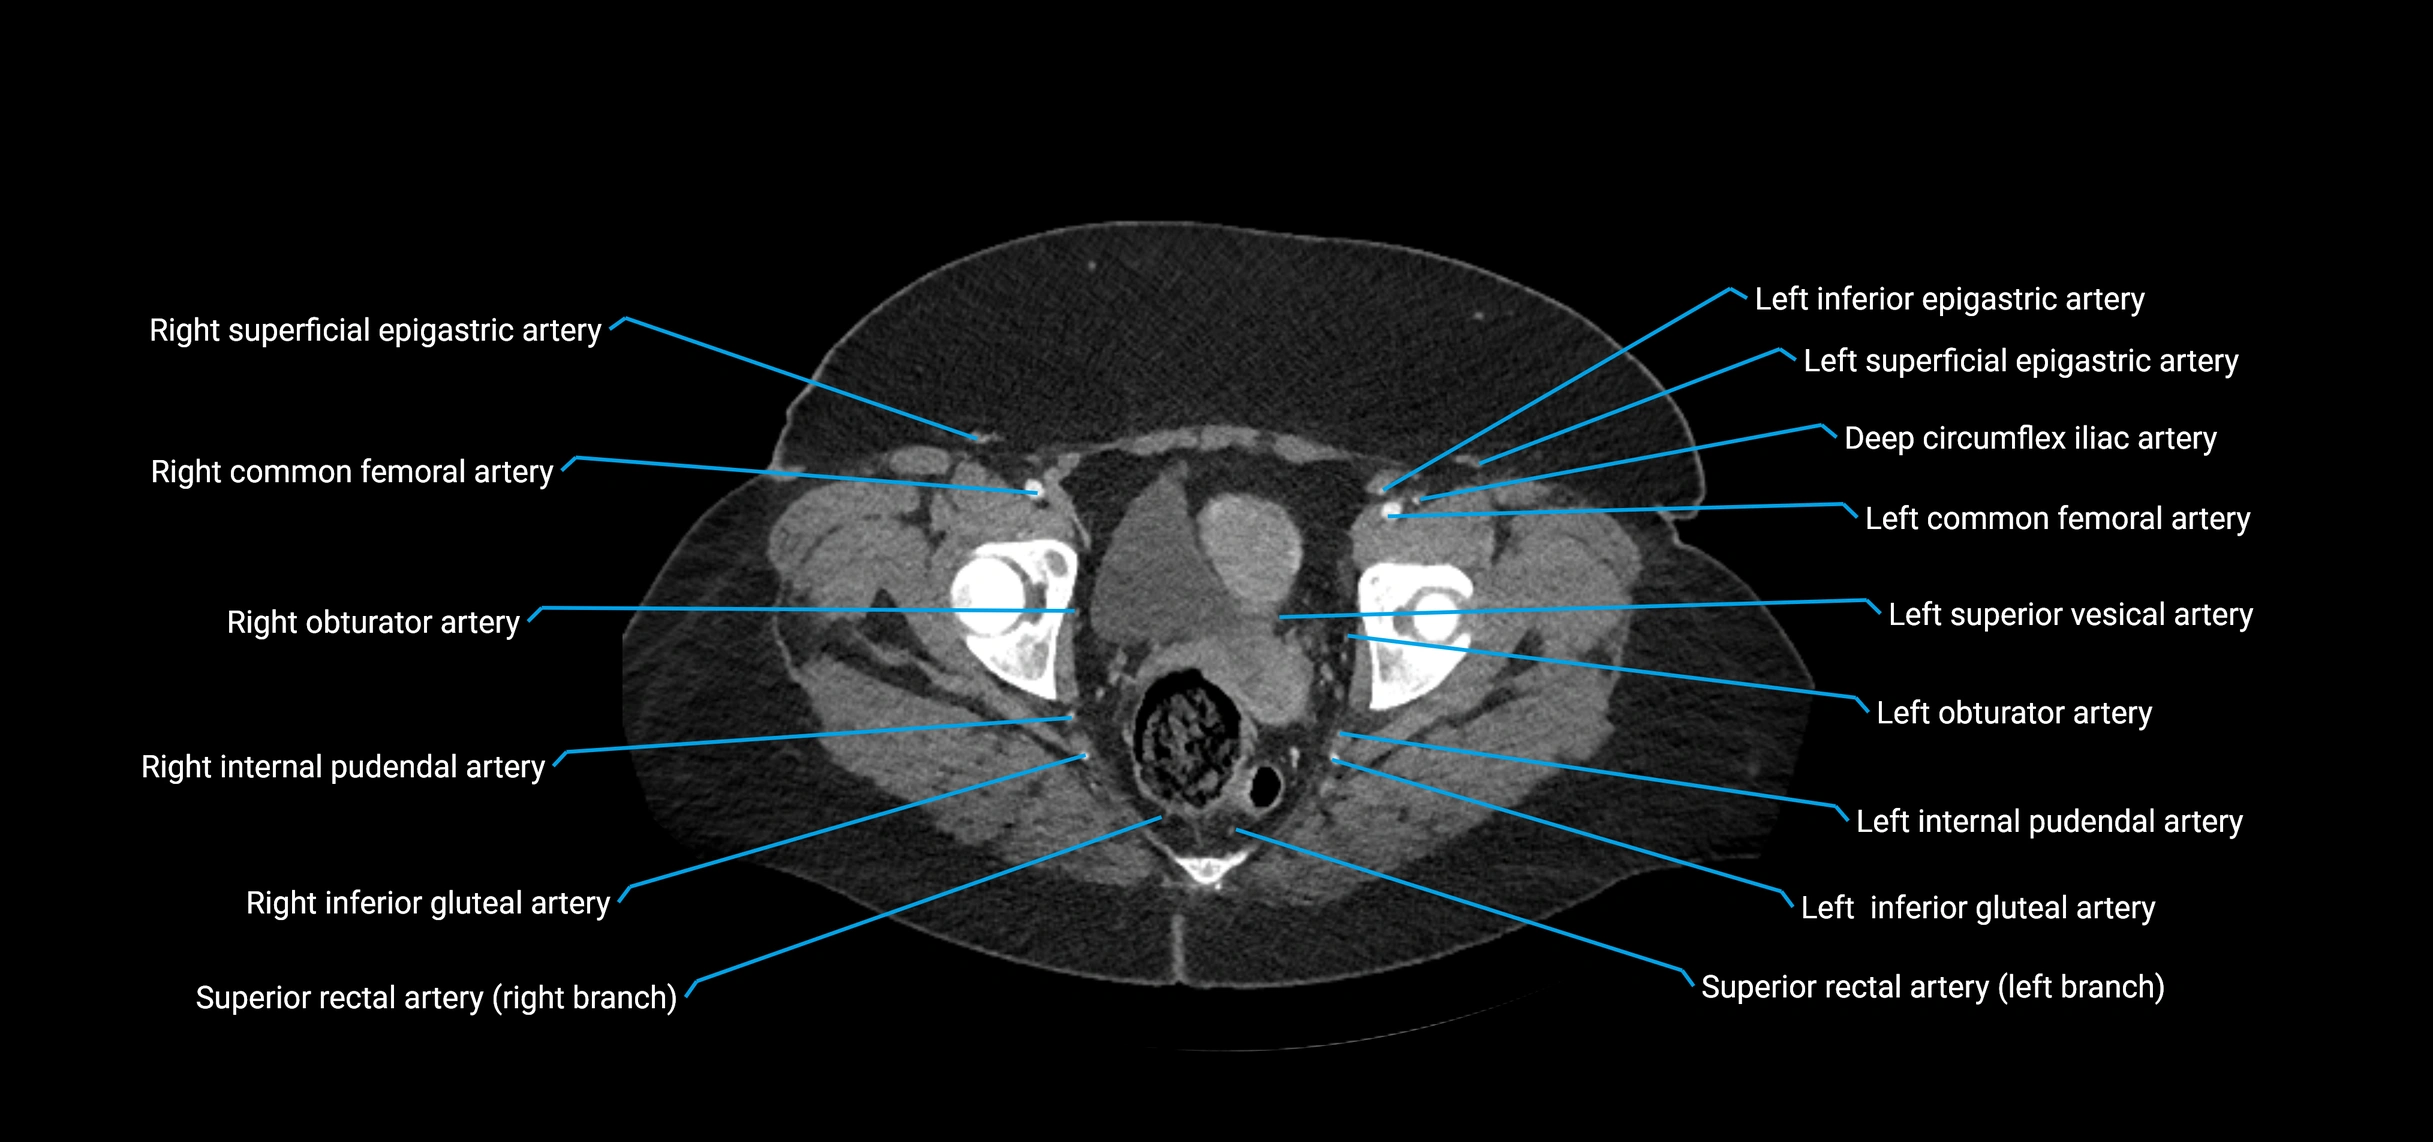

Contrast-enhanced CT (CTA):

• Gold standard for abdominal aortic imaging

• Provides excellent detail of lumen, wall, aneurysm, thrombus, and branch vessels

• Multiplanar and 3D reconstructions help in aneurysm measurement, stent graft planning, and dissection evaluation

• Detects acute rupture, traumatic injury, or occlusion with high sensitivity